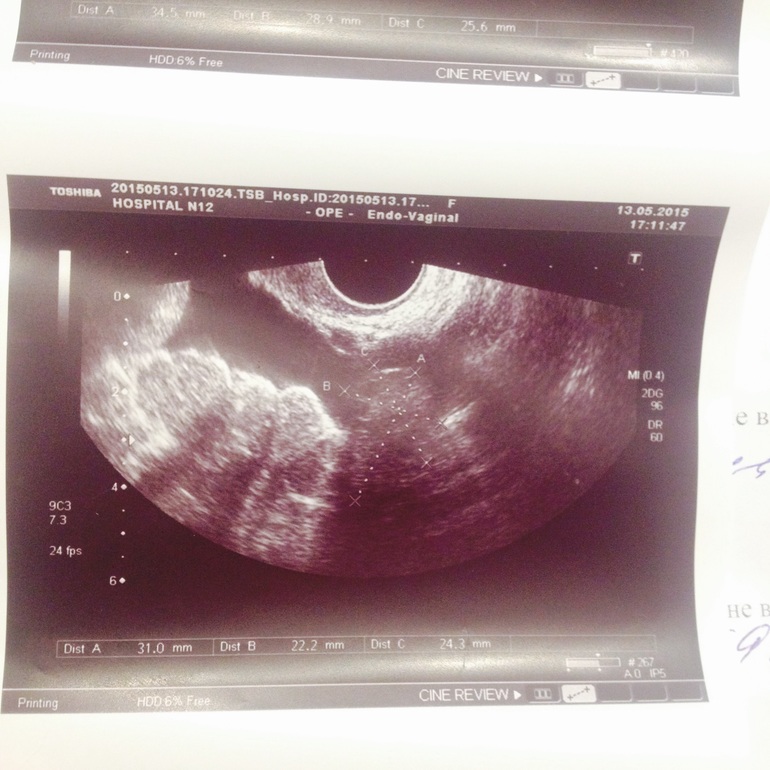

Сегодня ходила к врачу. Врач проверенный и хороший (записывалась через знакомых). Сделали узи. Эндометрий хороший, толстый. Ничего "криминального" не нашли. Плодное яйцо, конечно, пока не увидели...рановато. Врач сказала завтра пересдать хгч, на повторное узи через 10 дней. Говорит, что, возможно, организм только готовится к беременности. То есть, вот-вот может случиться, туманный альбион какой-то((( В общем, ничего не ясно. Буду ждать.

Фото узи под катом... что-то там отметили.